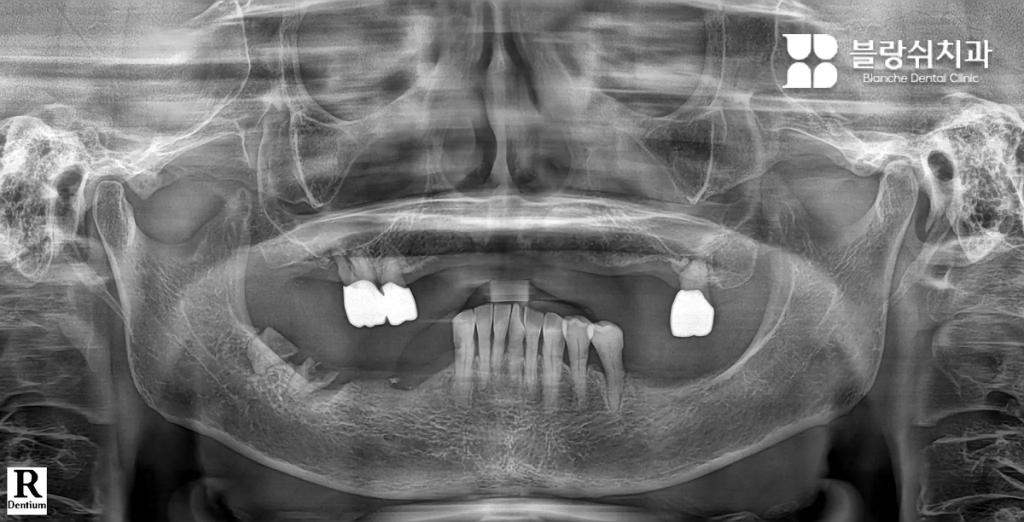

Case 1. 틀니와 장기 치료가 부담이었던 50대 남성

이 환자분은 여러 개의 치아 손상과 잇몸 약화로 인해 정상적인 저작이 어려운 상태였습니다. 전통적인 전체 임플란트를 고려했지만, 수개월에서 1년 이상 소요되는 치료 기간잇몸 절개 수술에 대한 부담으로 치료를 망설이고 계셨습니다. 특히 “잇몸을 크게 절개해야 한다”는 점이 가장 큰 두려움이었습니다.

• 디지털 풀아치 임플란트를 선택한 이유 인터넷 검색을 통해 디지털 풀아치 임플란트를 알게 되었고, 짧은 치료 기간과 최소 절개 수술이라는 점에 관심을 갖고 내원하셨습니다. 상담 과정에서 3D CT와 디지털 스캐닝을 통해 구강 상태를 정밀 분석했고, 임플란트 개수를 최소화하면서도 전체 치아 기능을 회복할 수 있는 구조라는 설명을 듣고 치료를 결정하셨습니다.

• 치료 후 변화 “이제는 음식 종류를 가리지 않고 먹을 수 있어서 삶의 만족도가 확실히 달라졌습니다.” 디지털 스캔 데이터를 기반으로 3D 치료 계획을 수립한 뒤, 컴퓨터 가이드 수술로 임플란트를 정확한 위치에 식립했습니다. 이후 CAD/CAM 기술로 제작된 풀아치 보철물을 장착하며 치료가 진행되었고, 적은 방문 횟수로 치료를 마칠 수 있었습니다.